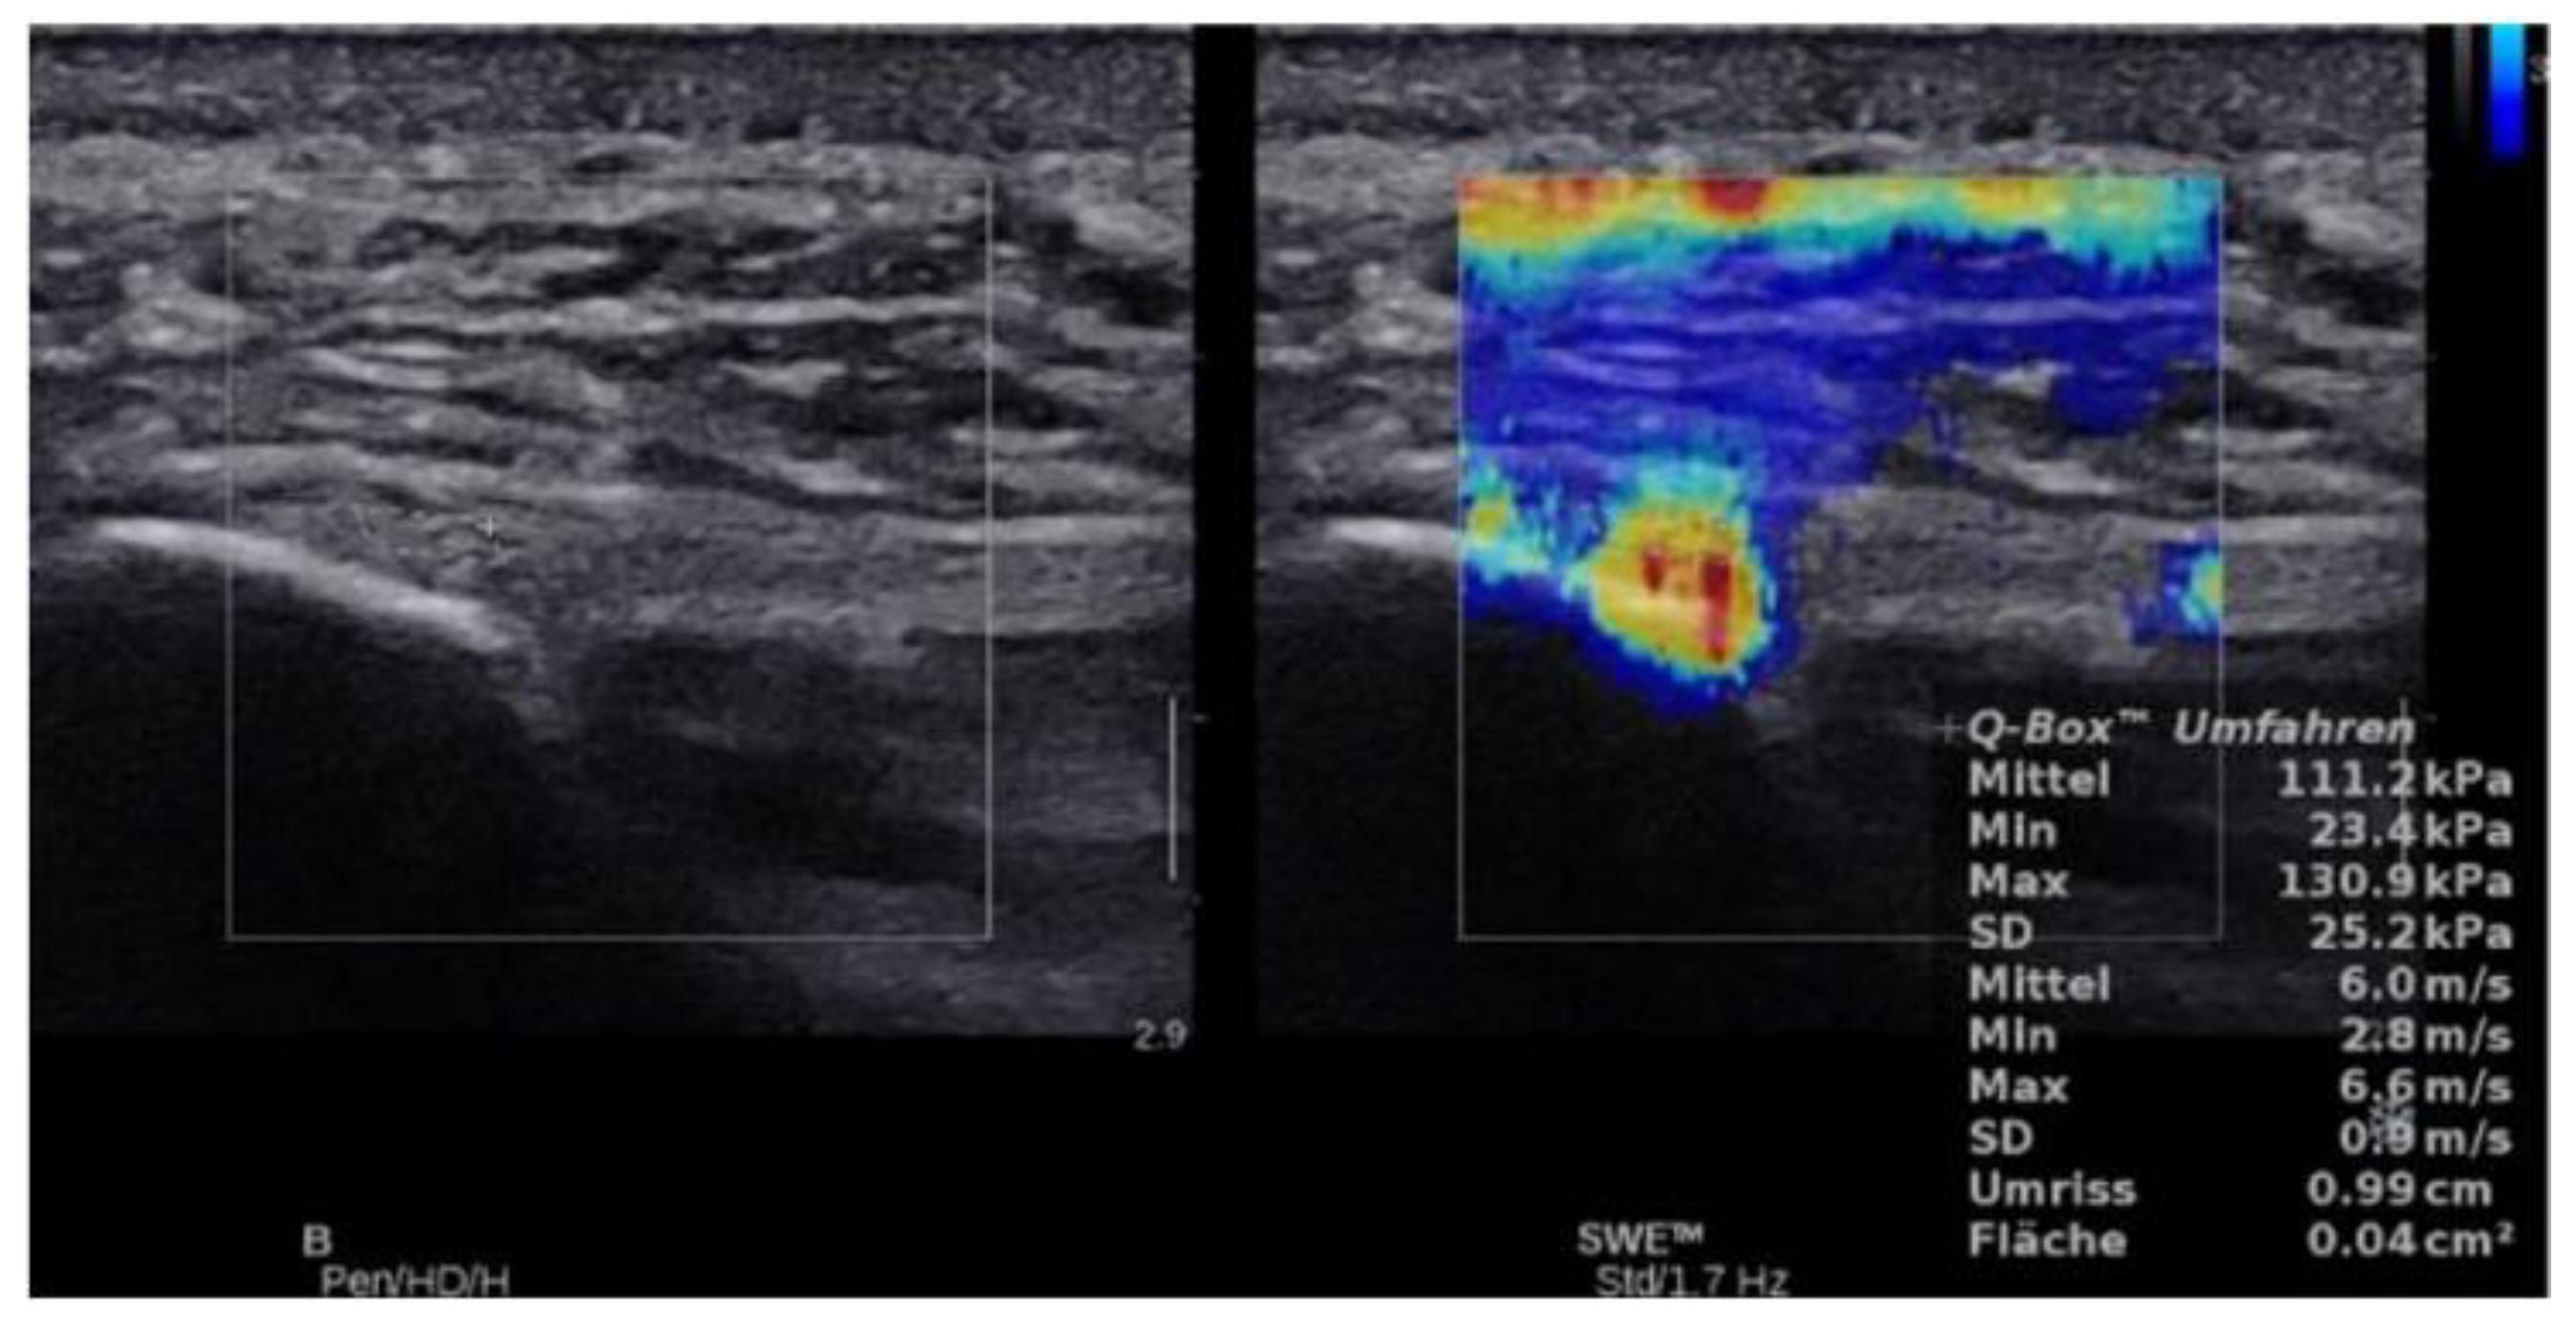

2.4.3. SWE Examination